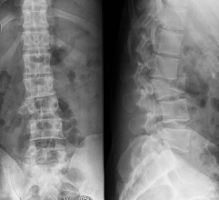

Scolioses

Les scolioses de l'adulte